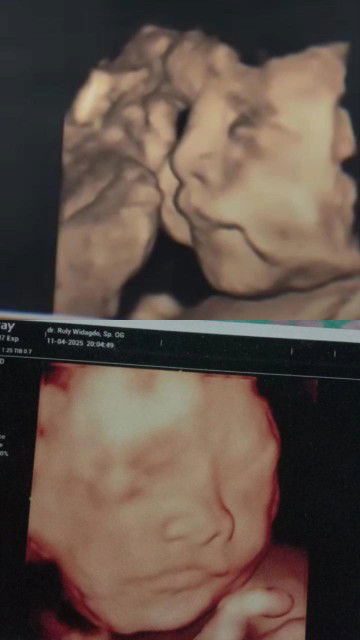

Moms, aku hamil 21w anak kedua dan ada riwayat SC pas lahiran anak pertama, hamil kedua ini kok beda bgt ya baru usia kandungan segini itu berasa perut kayak udah hamil 7bulan pas ngandung anak pertama, perut kencang terus aku ngerasa posisi janin itu agak kebawah pas diatas tulang miss v, klo nendang" jadi tulang miss v itu berasa ngilu padahal dulu hamil usia segini rasanya ga gini, apa karna efek udh pernah lahiran caesar otomatis rahim pernah robek karna di sayat jadi ngaruh? gmn ya menurut mom?#Sharingdong_Bund #bantujawab